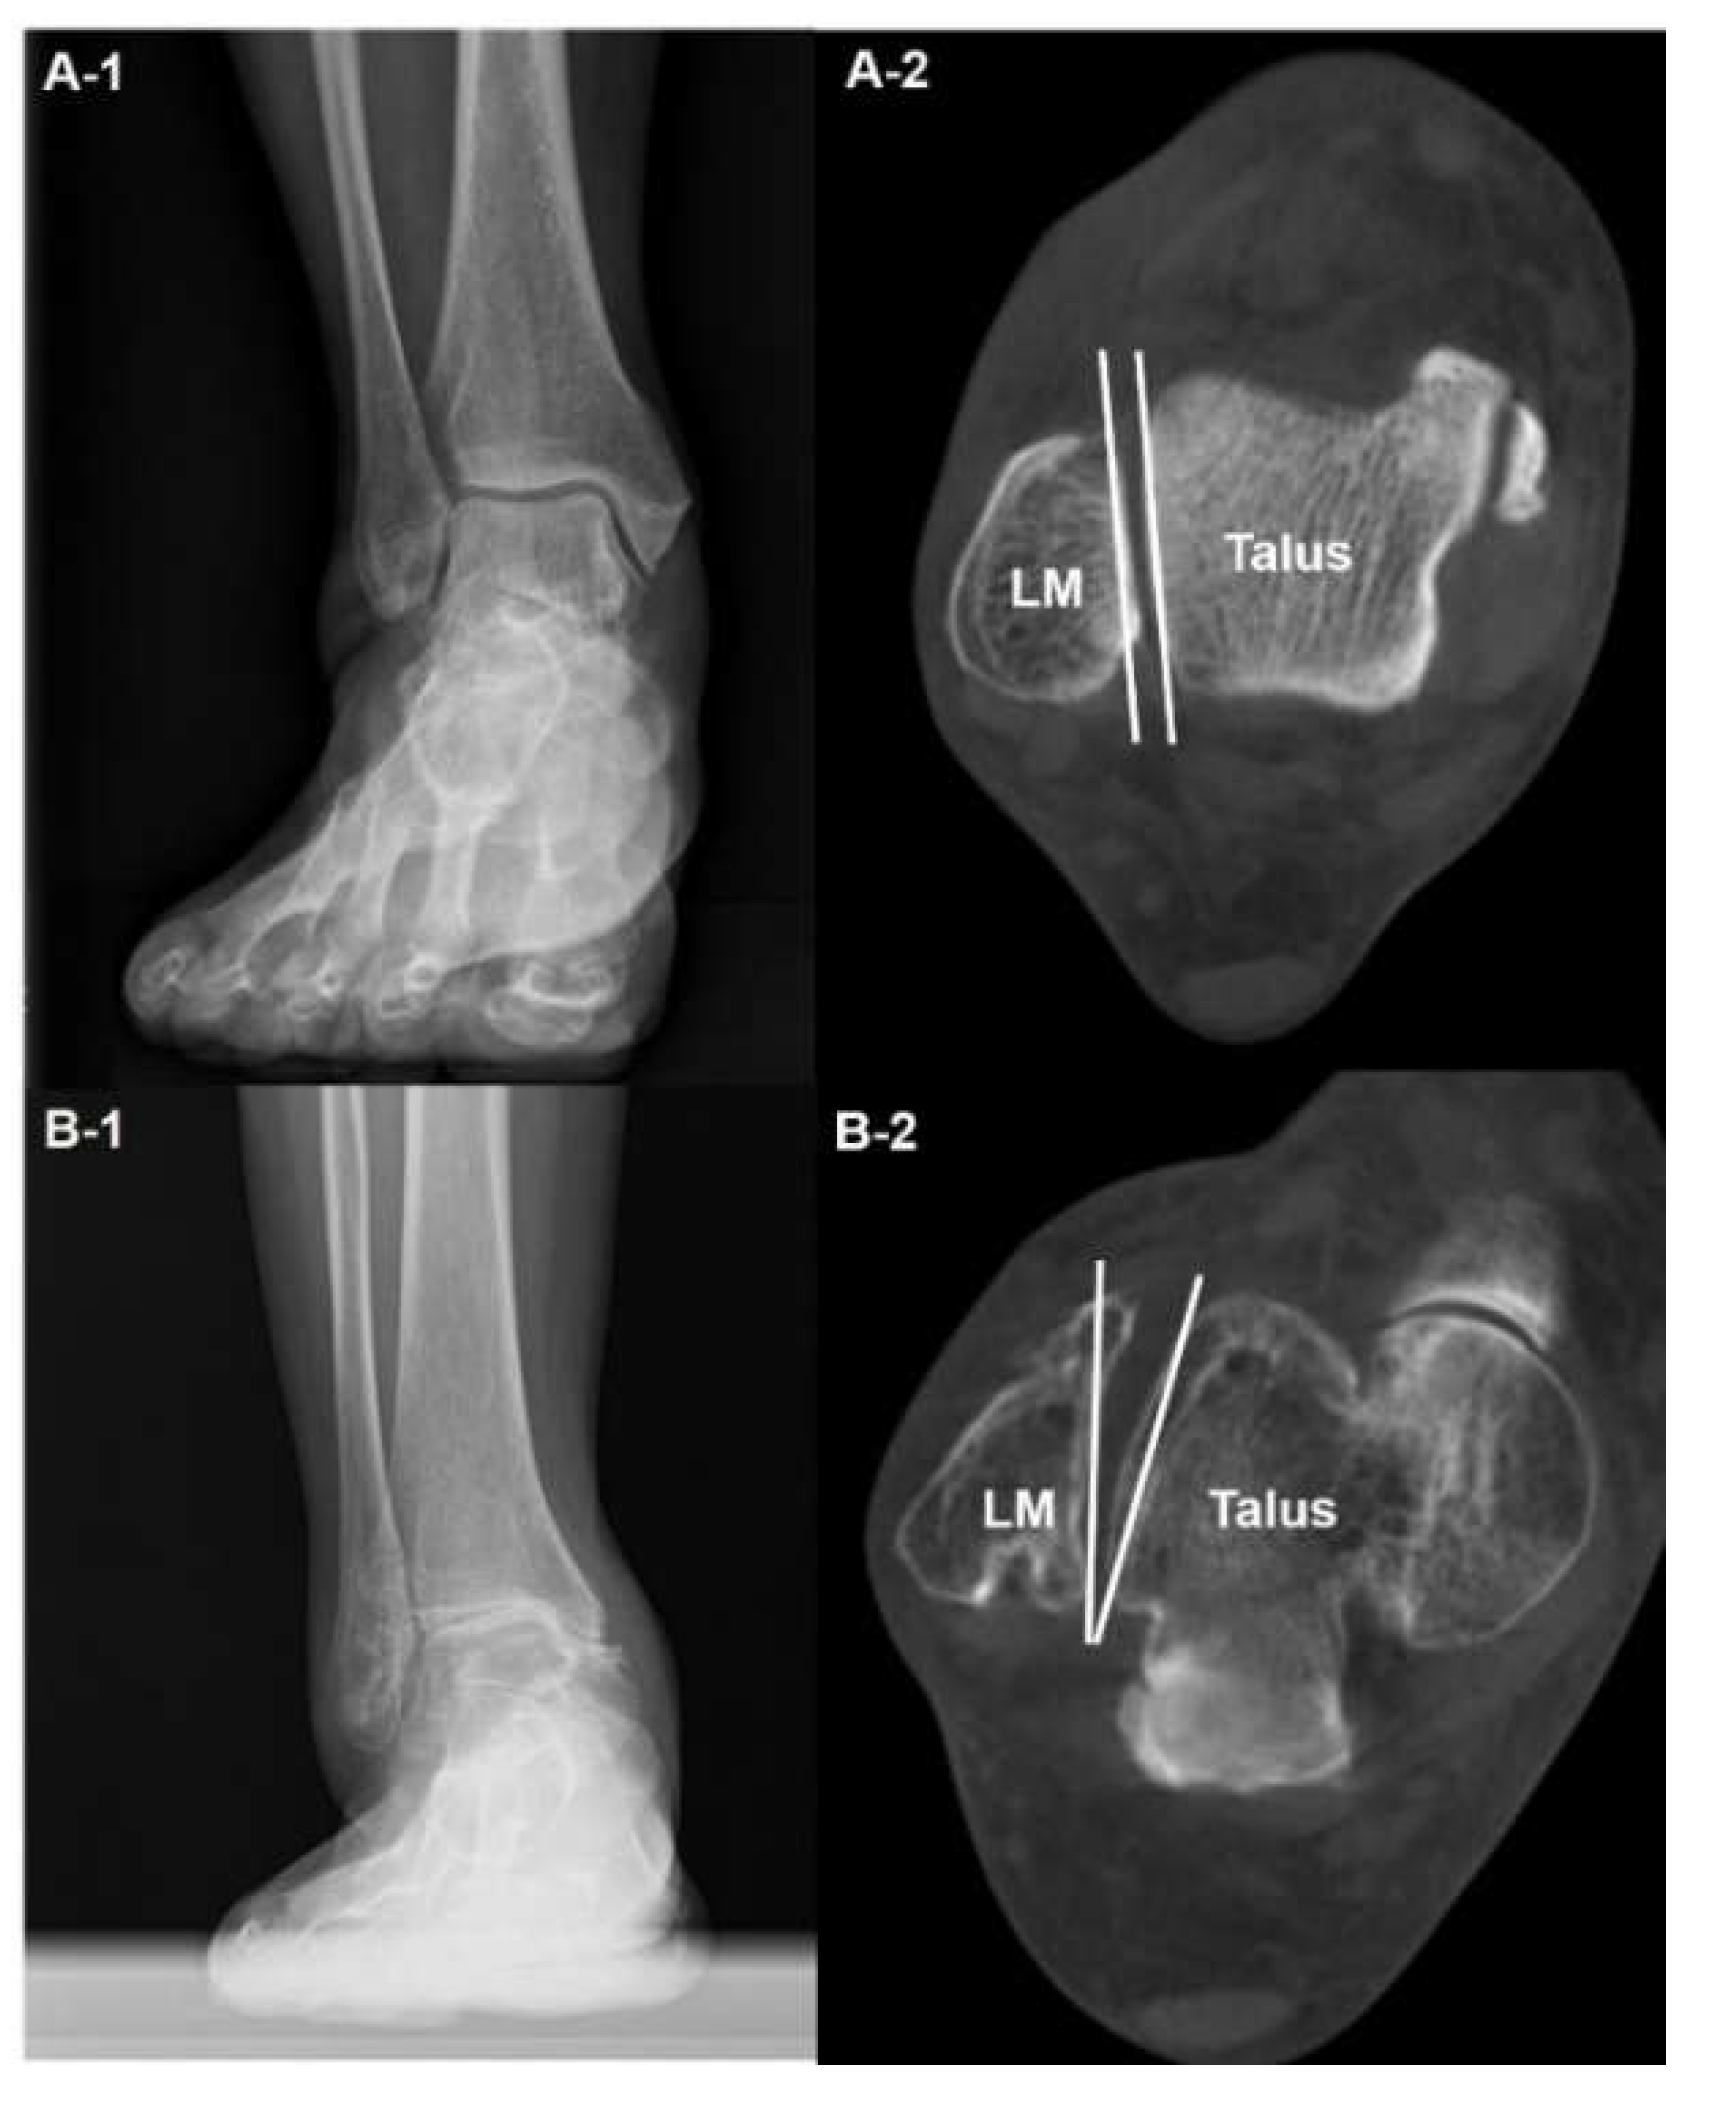

The use of WBCT in the diagnosis of ankle OA begins with a stereotaxic understanding of the position of the talus relative to the ankle mortise. The amount of pathologically altered ankle structure may suggest severity of ankle arthritis. Kim et al used talus rotation ratio to quantify abnormal internal rotation of the talus and concluded that the talus is abnormally internally rotated in patients with varus ankle arthritis [10]. They also added that patients with severe varus ankle osteoarthritis showed a higher incidence of abnormal talus internal rotation compared with those with moderate varus ankle osteoarthritis (Figure 1). Song et al evaluated the amount of correction after SMO using an axial loading CT, which showed significantly corrected abnormal internal rotation of the talus [4]. These findings indicate that not only the coronal and sagittal pathologic components of the ankle OA that can easily be visualized with conventional radiographs, but the axial component which can only be obtained with WBCT should also be considered to evaluate the disease.

Figure 1. Abnormal internal rotation of talus in the axial plane in varus ankle arthritis. Plain weight-bearing anteroposterior ankle radiography of the normal ankle (A-1) with corresponding WBCT axial image showing the congruent position of the talus in the ankle joint, without rotation against the lateral malleolus (LM) (A-2). Plain weight-bearing anteroposterior ankle radiography of a patient with varus ankle osteoarthritis (B-1), with WBCT axial image showing the internally rotated talus against the lateral malleolus (LM) (B-2).